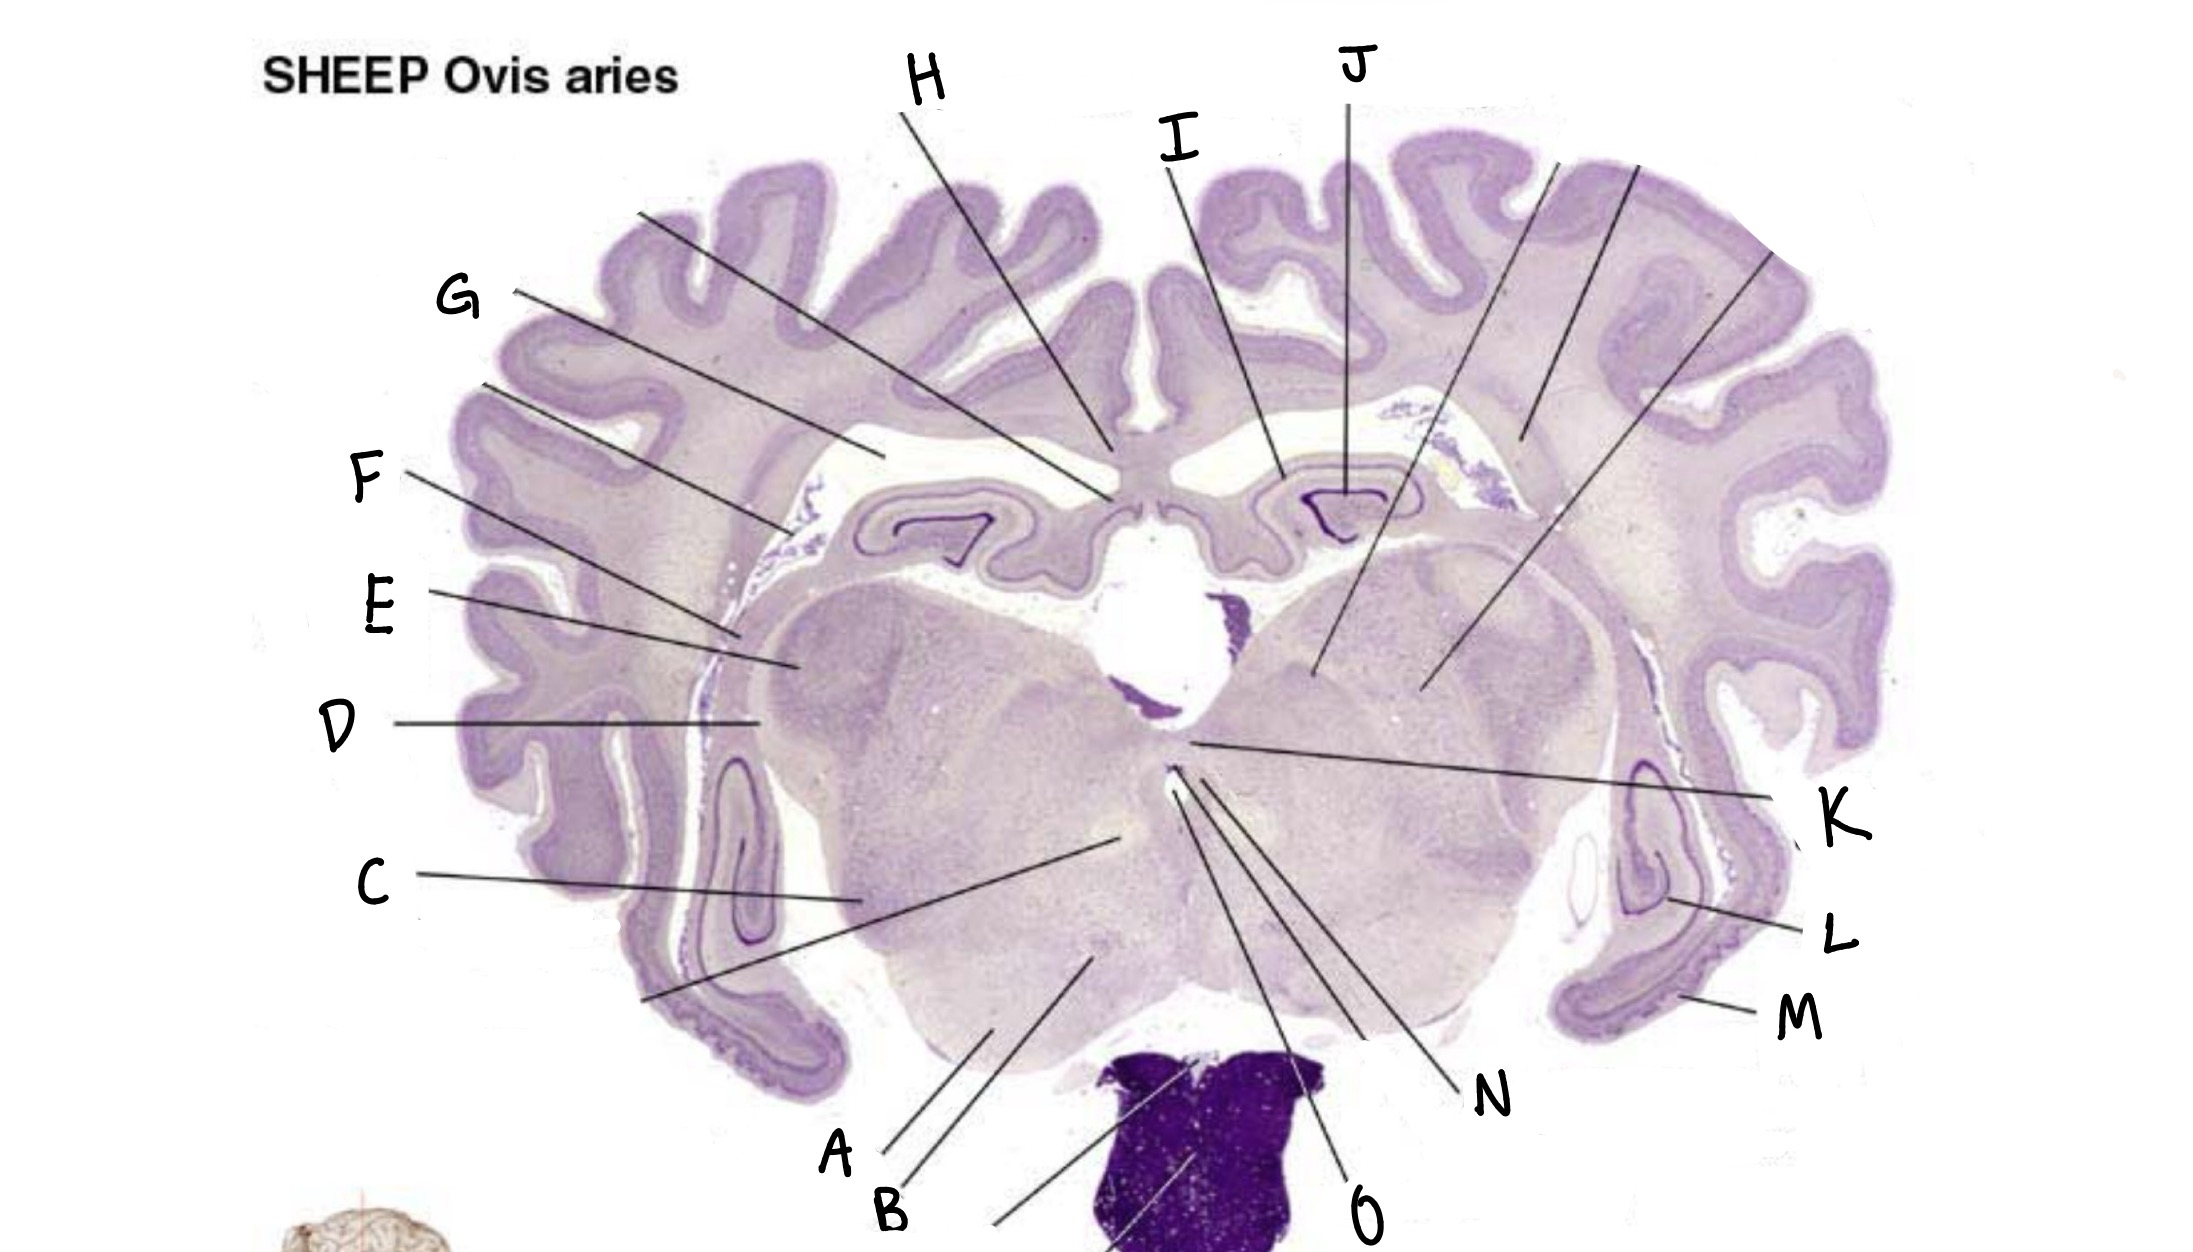

what is A

lateral ventricles

What is B

cingulate gyrus

what is c

corpus callosum

what is d

septum

what is e

putamen

what is f

third ventricle

what is g

optic chiasm

what is h

anterior commissure

what is i

caudate

what is j

rhinal fissure